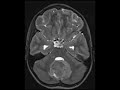

Medulloblastoma

These images show a large mass in the posterior fossa in a pediatric patient which demonstrates heterogeneous enhancement and restricted diffusion. There is significant mass effect on the inferior brainstem resulting in crowding of the foramen magnum. Mild perilesional T2 FLAIR hyperintensity is compatible with vasogenic edema. CT which is not depicted here shows the mass to be hyperdense. Findings are compatible with a medulloblastoma which was proven on pathology. Medulloblastomas are WHO grade IV with 4 major molecular subgroups with varying prognoses. This particular mass was positive for the Sonic Hedgehog (SHH) subtype which has an intermediate prognosis.